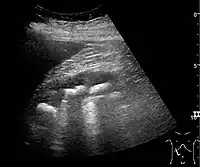

![]() Doppler ultrasound (US) of a normal adult kidney with the estimation of the systolic velocity (Vs), the diastolic velocity (Vd), acceleration time (AoAT), systolic acceleration (Ao Accel) and resistive index (RI). Red and blue colors in the color box represent flow towards and away from the transducer, respectively. The specrogram below the B-mode image shows flow velocity (m/s) against time (s) obtained within the range gate. The small flash icons on the spectrogram represent initiation of the flow measurement.[1] | |

Doppler ultrasonography of the kidney is widely used, and the vessels are easily depicted by the color Doppler technique in order to evaluate perfusion. Applying spectral Doppler to the renal artery and selected interlobular arteries, peak systolic velocities, resistive index, and acceleration curves can be estimated (Figure 4) (e.g., peak systolic velocity of the renal artery above 180 cm/s is a predictor of renal artery stenosis of more than 60%, and a resistive index, which is a calculated from peak systolic and end systolic velocity, above 0.70 is indicative of abnormal renovascular resistance).[1]